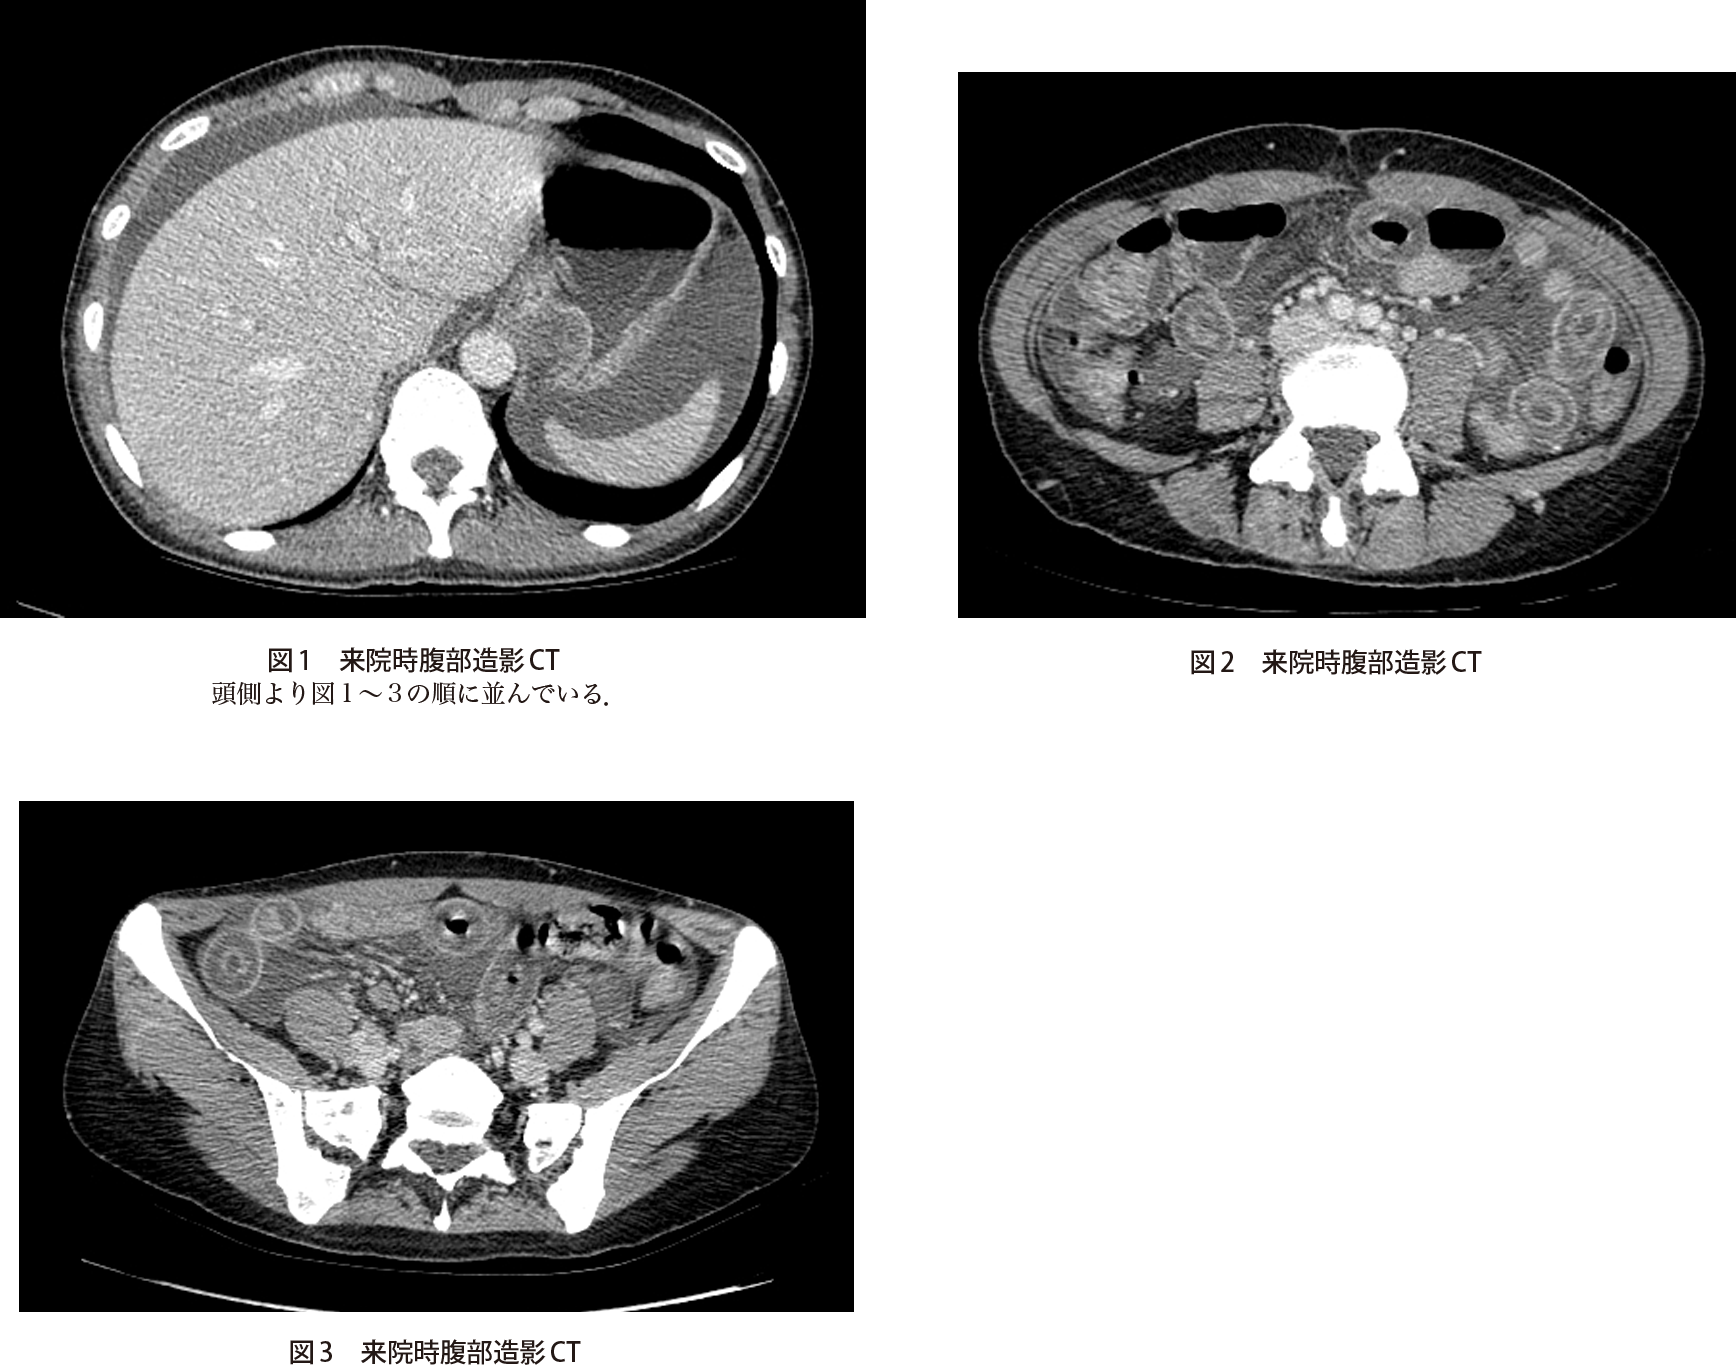

腹痛 嘔気 嘔吐を主訴に来院した40歳代女性 実践 画像診断q A 羊土社 レジデントノート 羊土社